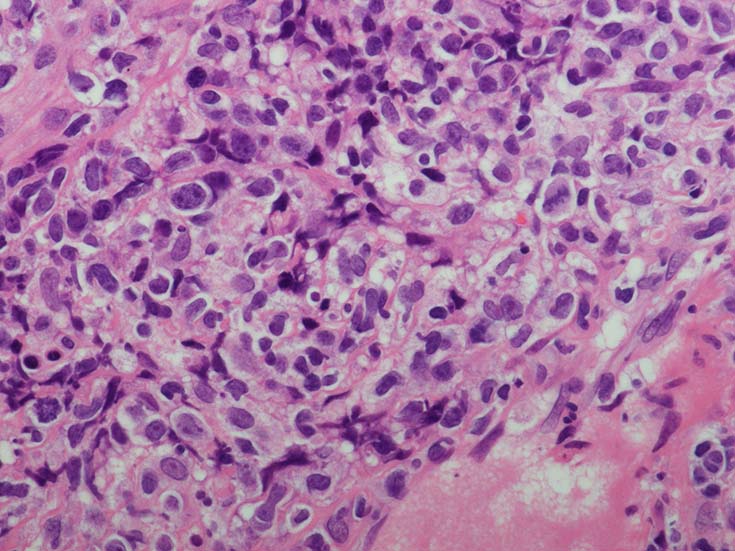

EBUS-GS(ガイドシース併用気管支腔内超音波断層法)による肺生検組織病理所見.

血管周囲性に大型類円形核や不整形核をもつ腫瘍細胞がシート状密に浸潤増殖している. Mitosisが多く認められる.細血管閉塞や破壊の所見がある.

間質にもシート状の腫瘍細胞浸潤がある. 大小 pleomorphicな傾向.(A, B). necrosisが認められる(C). 細気管支上皮直下まで密な浸潤あり, 小型リンパ球が混在している.(D)

血管中心性浸潤. 障害された血管内に血栓が形成されている.CD20陽性細胞がシート状密に浸潤, CD3陽性T細胞が多く混在している. EBER-ISH陽性 EBV感染細胞が多数認められ, >50 hpf, 定義より Grade3となる. 陽性細胞のサイズは大小さまざまであることに注意. Lymphomatoid granulomatosisの病態(WHO5thの診断では EBV-positive diffuse large B-cell lymphomaになる)をとっているが MTX-associated LPDの一型とするべき症例かもしれません.